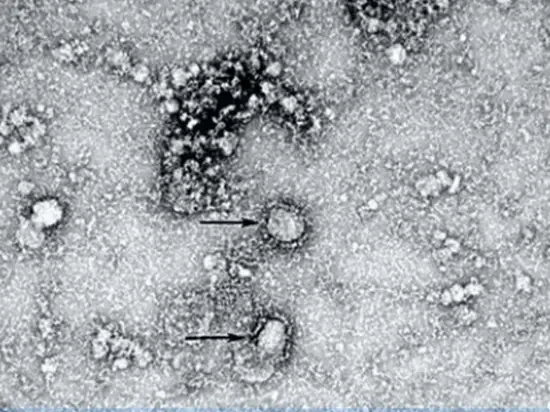

Қытай ғалымдары жаңа коронавирусты суретке түсіріп алды